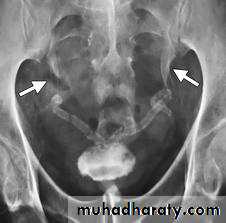

Renal TB:

GU tract second most common site of tuberculous infection after lungs, 2ndry to TB infection everywhere.

Spread is hematogenous

Features :

Plain films may show large globular, a morphous calcificationsIVU :

Cortical scarring

"Smudged" papillae (moth-eaten) –irregular due to inflammation and necrosis

Infundibular strictures

Hydrocalyces without dilatation of renal pelvis or Hydronephrosis

Autonephrectomy – small, shrunken kidney with dystrophic calcification

When ureters are involved, usually the upper or lower third (more common)

Bladder involvement rarely leads to calcification of wall (think histosomiasis)